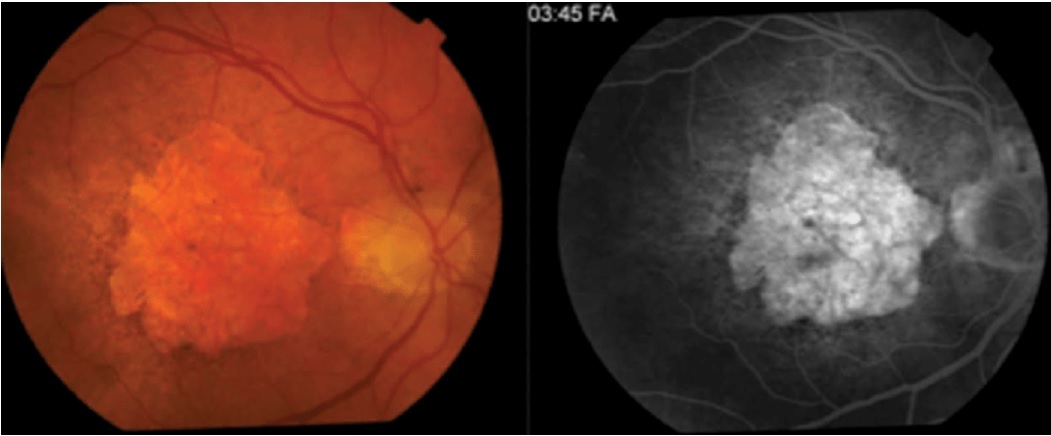

Qual é a classifcação da DMRI Exsudativa, de acordo com a AGF?

Oculta (87%):

Clássica (13%)

Quais são achados típicos no exame fundoscópico que sugerem DMRI Exsudativa?

Extravasamento (exsudatos, edenma macular)

Hemorragias

Cicatriz disciforme